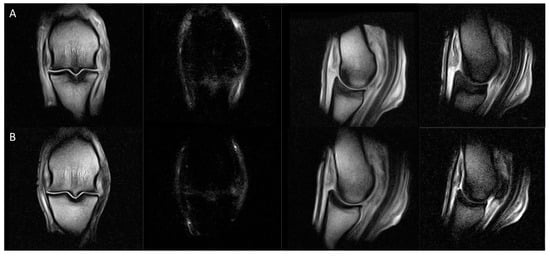

| SGD MRI Classification | Sub-Classifications and Description of Key Osseous Changes in the Sagittal Groove of the Proximal Phalanx | Absent Concurrent Features | Potential Concurrent Features | |

|---|---|---|---|---|

| 0 | Normal | No abnormalities | N/A | N/A |

| 1 | Small subchondral defect | (a) Minor, shallow defect in the chondro-osseous junction (typically ≤1 mm depth ± visible in only one slice) | Demineralisation, osseous densification, bone oedema-like signal | N/A |

| (b) Microfissure (proximodistally oriented, narrow, linear defect in the chondro-osseous junction that is contained within the subchondral bone plate, ≤3 mm length) | ||||

| 2 | Osseous densification | (a) Mild osseous densification of the subchondral ± trabecular bone, not extending to the proximal physis/physeal scar (proximodistal extent less than the equivalent depth of the SG) | Microfissure, demineralisation, bone oedema-like signal | Minor subchondral defect |

| (b) Moderate to severe osseous densification of the subchondral ± trabecular bone, extending to or beyond the proximal physis/physeal scar (proximodistal distance greater than one times the depth of the SG) | ||||

| 3 | Subchondral microfissure with osseous densification | (a) Subchondral microfissure (≤3 mm length) with mild osseous densification (does not reach the proximal physis/physeal scar) | Subchondral demineralisation or bone oedema-like signal | |

| (b) Subchondral microfissure (≤3 mm length) with moderate to severe osseous densification (extending to or beyond the proximal physis/physeal scar) | ||||

| 4 | Bone oedema-like signal within the subchondral ± trabecular bone | (a) Bone oedema-like signal within the subchondral ± trabecular bone | Microfissure, demineralisation | Minor subchondral defect, osseous densification of any extent |

| (b) Bone oedema-like signal within the subchondral ± trabecular bone with microfissure (short proximodistally oriented, narrow, linear defect contained within the subchondral bone plate (≤3 mm)) | Demineralisation | Osseous densification of any extent | ||

| (c) Bone oedema-like signal within the subchondral ± trabecular bone with subchondral demineralisation (unipartite or tripartite regions of demineralisation/resorption within the subchondral bone plate) | Microfissure, osseous densification of any extent | |||

| 5 | Incomplete macrofissure/fracture | Proximodistally oriented linear signal abnormality (>3 mm length; unipartite or tripartite configuration) extending through the subchondral bone and terminating within the trabecular bone | N/A | Demineralisation, osseous densification or bone oedema-like signal of any extent |

| 6 | Complete fracture | Proximodistally oriented linear signal abnormality extending through the subchondral and trabecular bone and exiting at the diaphyseal cortex or distal subchondral bone plate with the creation of two or more fragments | N/A | Demineralisation, osseous densification or bone oedema-like signal of any extent |